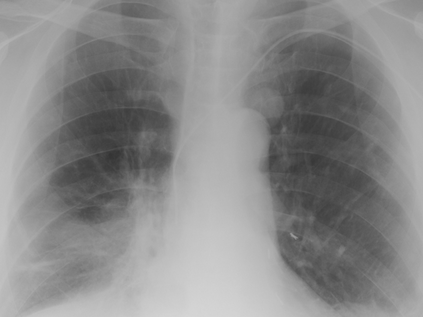

Tuberculosis remains a critical global health issue, particularly in resource-limited and remote areas. Early detection is vital for treatment, yet the lack of skilled radiologists underscores the need for artificial intelligence (AI)-driven screening tools. Developing reliable AI models is challenging due to the necessity for large, high-quality datasets, which are costly to obtain. To tackle this, we propose a teacher--student framework which enhances both disease and symptom detection on chest X-rays by integrating two supervised heads and a self-supervised head. Our model achieves an accuracy of 98.85% for distinguishing between COVID-19, tuberculosis, and normal cases, and a macro-F1 score of 90.09% for multilabel symptom detection, significantly outperforming baselines. The explainability assessments also show the model bases its predictions on relevant anatomical features, demonstrating promise for deployment in clinical screening and triage settings.